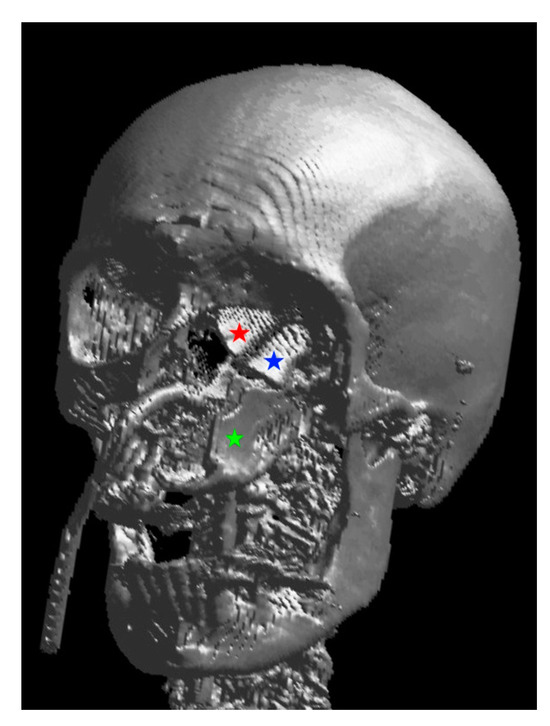

Here, support and volume are required to obtain an aesthetically pleasing and functional reconstruction. A DCIA with internal oblique muscle and skin in conjunction with an MFC (or a perforator flap) can satisfy the above requirements. The DCIA replaces the maxilla, while the MFC reconstructs the orbital walls, as seen in the patient below (Figure 1, Figure 2, Figure 3, Figure 4, Figure 5 and Figure 6).

Figure 3. Three-dimensional rendering of the reconstruction: the red star marks the neo-medial wall, the blue star the neo-orbital floor, both belong to the MFC flap, and the green star marks the vertically oriented DCIA flap.